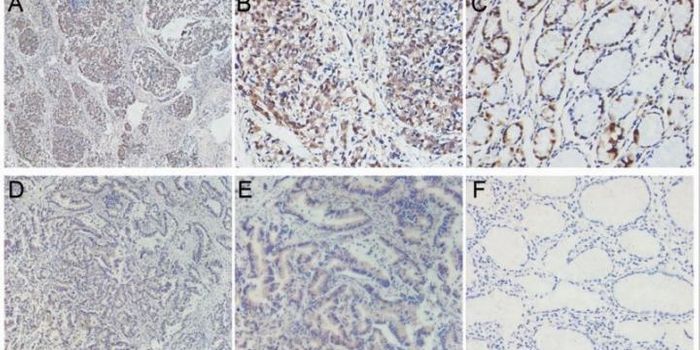

FEB 09, 2024CancerHistopathology describes the process of examining pieces of tissue using a microscope. Light microscopic (LM) exam ...